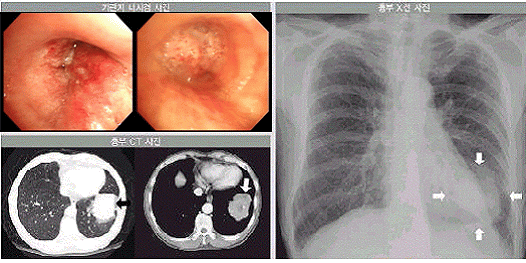

기관지내시경검사

기관지에 내시경을 넣어서 암 조직의 기관지 침범 여부를 확인할 수 있으며, 병변이 관찰될 경우 기관지 내시경을 통하여 겸자(forcep, 날이 없는 기다란 가위같이 생긴 도구) 등의 기계를 넣어 조직검사를 하거나 솔질(brushing, 솔로 쓸어 모으는 것) 등을 통하여 검사함으로써 암을 확진할 수 있습니다. 육안상 기관지를 얼마나 침범했는지를 확인할 수 있으므로 수술 등 치료 계획을 세우는 데 도움을 줍니다.

폐암의 기관지내시경검사, 흉부 전산화단층촬영(CT), 그리고 단순 X-선 촬영 소견 이미지

[폐암의 기관지내시경검사, 흉부 전산화단층촬영(CT), 그리고 단순 X-선 촬영 소견]